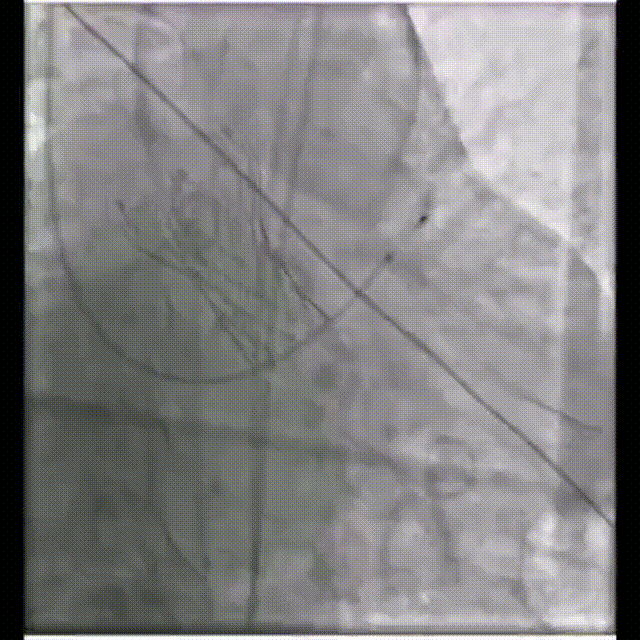

主动脉根部造影

22mm球囊预扩

输送器过弓

瓣膜回收再定位

26mm瓣膜释放

术后造影